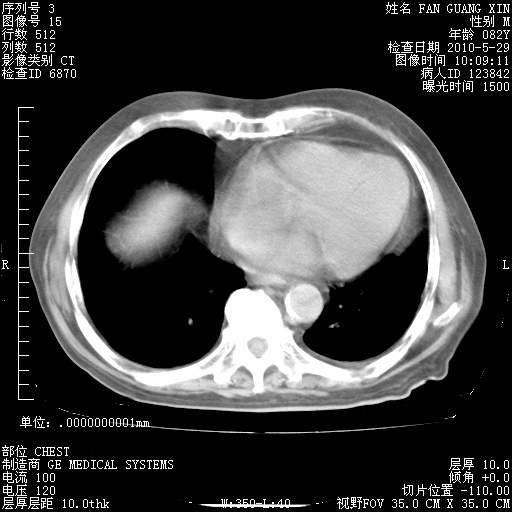

再治疗10天后的肺部CT

再治疗10天后的肺部CT 纵膈窗

阅读此次胸部CT,肺间质渗出性改变较入院时有吸收。目前从体温、白细胞、中性分叶明显增高,肯定存在细菌感染(发生医院感染哦,若无消化道及泌尿系统等感染的依据,肺部感染可能大)。若你院头孢哌酮舒巴坦钠耐药率较高,同意你的方案,若48小时体温仍高,可考虑使用碳青霉稀类抗菌药物,同时可予超声雾化、注意滴数时加大液体量。白蛋白33.30g/L较低哦,需加强营养等支持治疗。